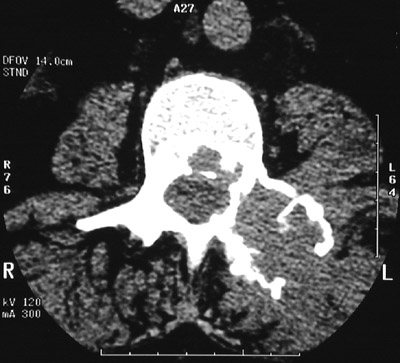

| The destructive, expansile lytic lesion seen above involving the L2 vertebral pedicle on the left with an abdominal CT scan is a solitary plasmacytoma. A closer CT view is shown below. In this case, there was no increase in serum IgG and no monoclonal "spike" on either serum or urine protein electrophoresis. |